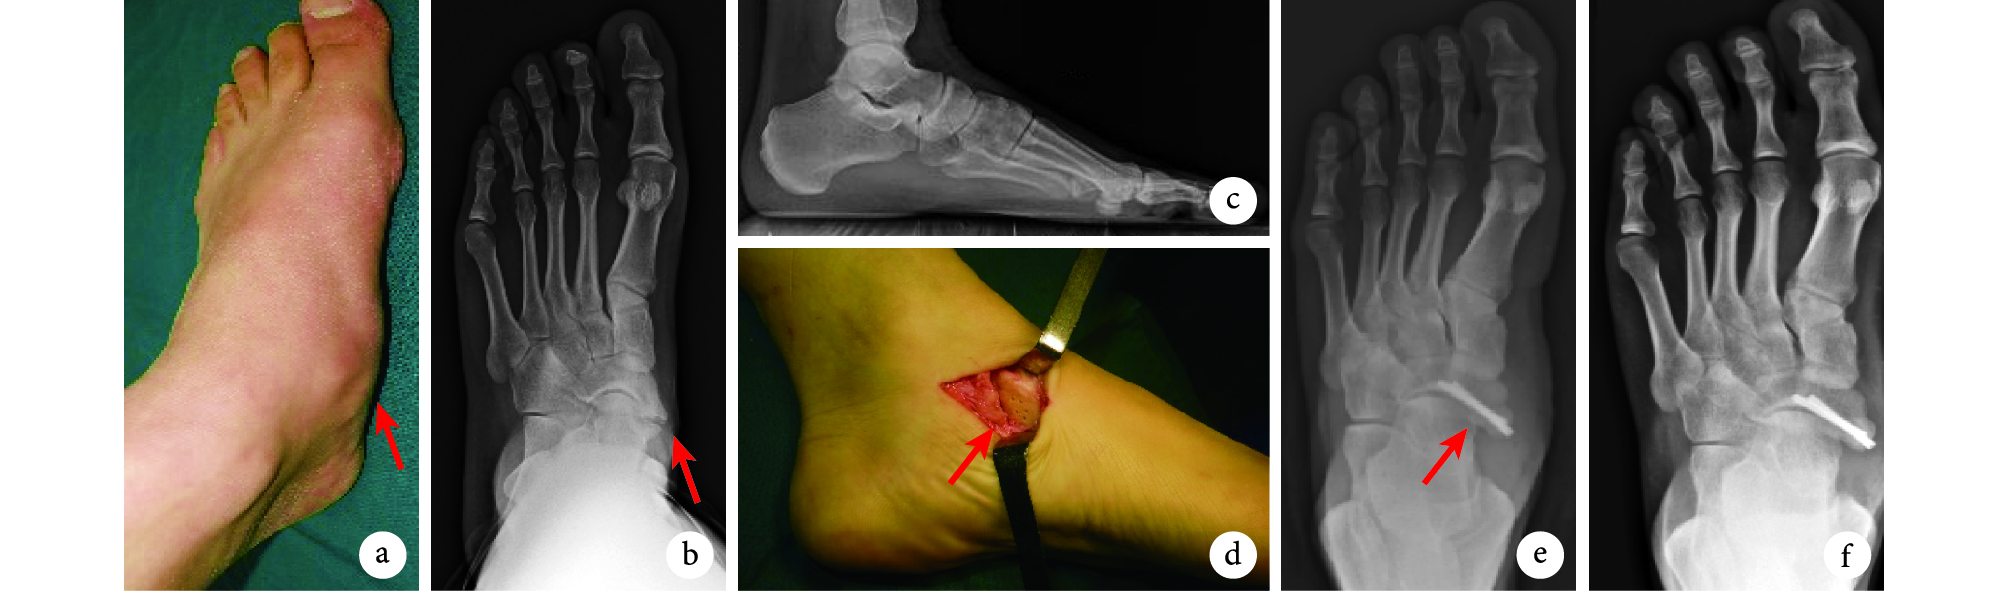

a. 術前外觀 箭頭示足副舟骨隆起部分;b、c. 術前正側位 X 線片 箭頭示足副舟骨與舟骨間聯合處;d. 術中外觀 箭頭示截骨后舟骨與足副舟骨關節面;e. 術后 1 個月正位 X 線片 箭頭示舟骨與足副舟骨關節面對位固定良好;f. 術后 6 個月正位 X 線片

Figure1. A 25-year-old male patient with left type Ⅱ PANa. Preoperative appearance Arrow indicated the accessory scaphoid eminence; b, c. Anteroposterior and lateral X-ray films before operation Arrow indicated the joint of the accessory scaphoid and the scaphoid; d. Intraoperative appearance Arrow indicated the articular surfaces of scaphoid and accessory scaphoid after osteotomy; e. Anteroposterior X-ray film at 1 month after operation Arrow indicated that the articular surfaces of the scaphoid and the accessory scaphoid were fixed well; f. Anteroposterior X-ray film at 6 months after operation